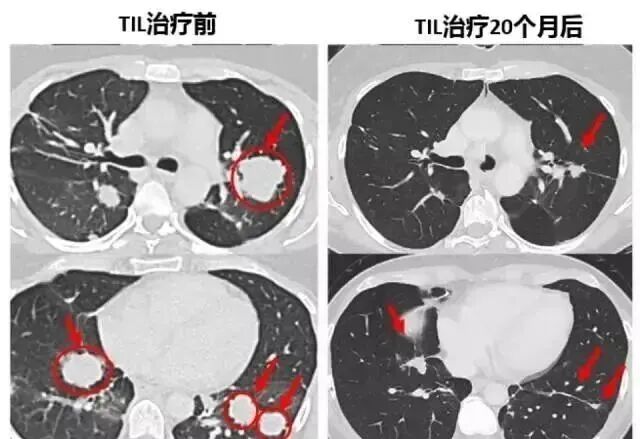

第二次回输超过1000亿个专门识别肿瘤细胞的免疫细胞战士浩浩荡荡的地进入了Melinda的体内。效果真的惊人!她全身肿瘤开始迅速缩小,体力恢复很快。

下面的对照图可以非常明显看到,第二次治疗前肺部布满的肿瘤,包括一些个头非常大的,第二次TIL细胞治疗20个月后复查,这些肿瘤都竟然都明显的缩小了。

虽然Bachini体内的肿瘤还没有完全消失,但这个致命的肿瘤确实在一天天缩小,TIL免疫细胞疗法,让Bachini恢复了正常人的生活,现在9年过去了,她还是如往常一般生活着,免疫细胞疗法无疑给她的人生带来了重大转折。